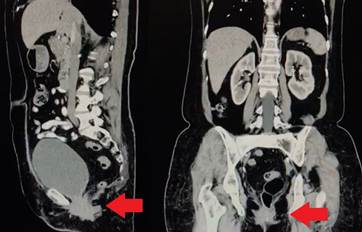

Se trata de una paciente femenina de 64 años, con antecedente de histerectomía por abordaje abdominal 35 años atrás y sin otros antecedentes de importancia. Consultó por presentar sensación de masa en la vagina. Inicialmente fue valorada por el servicio de ginecología, quienes encontraron un prolapso vaginal y abultamiento del labio mayor izquierdo. Ante estos hallazgos, se realizó una tomografía computarizada contrastada de abdomen donde se encontraron alteraciones compatibles con una hernia perineal (Figura 1).